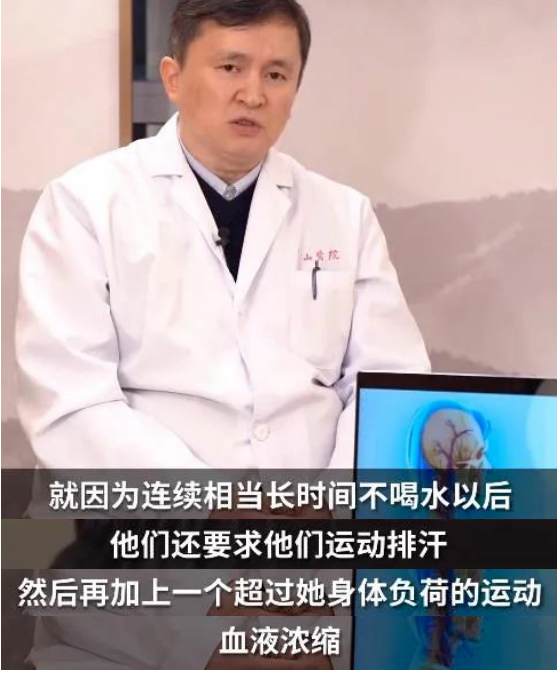

而这位美女之所以发病,

是因为作为模特上台之前

需要控制体重,

“一段时间内”没有喝水,

导致血液浓缩,

加上超身体负荷的运动造成的。

医生在诊治后

还发现这位模特本身患有

“ 烟雾病 ”

烟雾病是一种病因不明的、以双侧颈内动脉末端及大脑前动脉、大脑中动脉起始部慢性进行性狭窄或闭塞为特征,并继发颅底异常血管网形成的一种脑血管疾病。由于这种颅底异常血管网在脑血管造影图像上形似“烟雾”,故称为“烟雾病”。